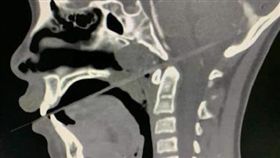

少女玩彈跳床癱床不起 醫驚見「腦滑出」

彈跳床活動不分國內外,都相當受到大人和小朋友喜愛,它...